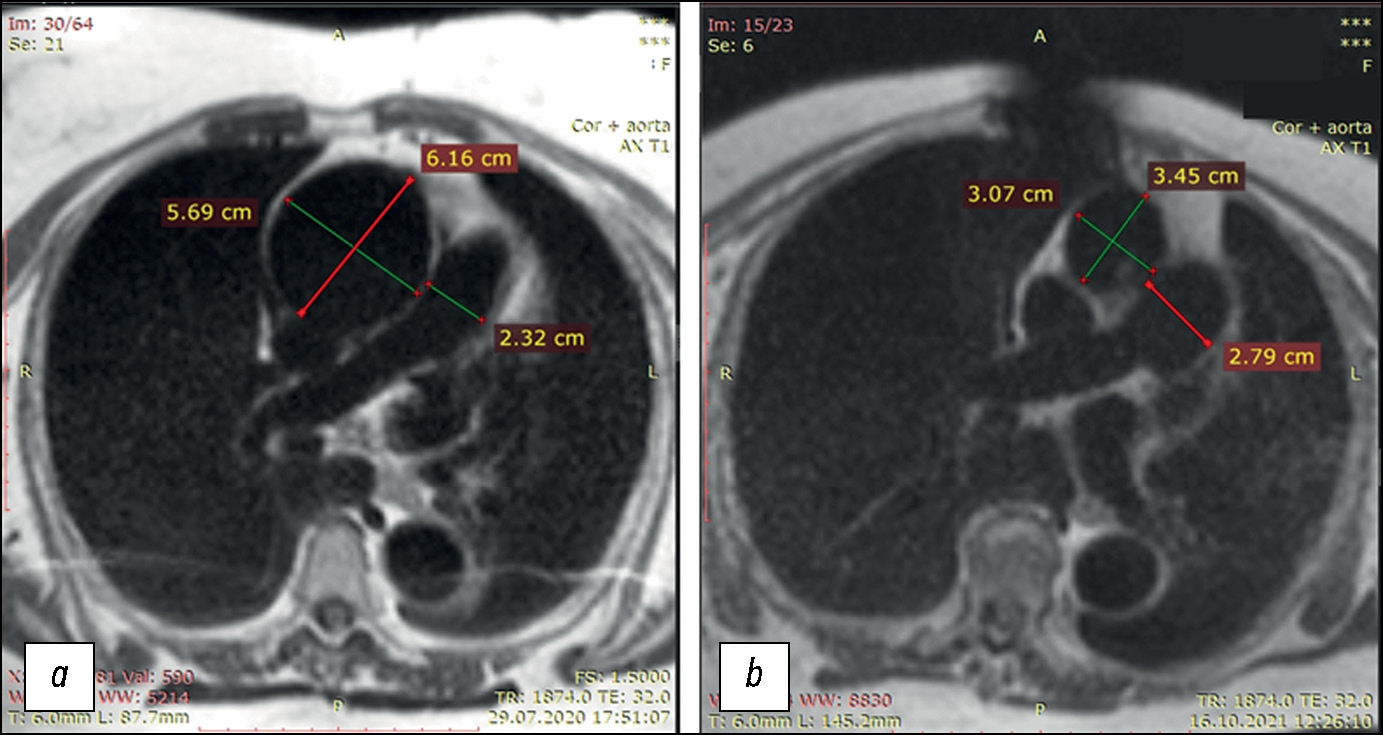

Prospective evaluation of the extensibility of the ascending aorta wall and its vascular prosthesis in a patient with an aneurysm with technically flawless surgical correction and postoperative decrease in functional parameters: A case report

Abstract

In this clinical case, a patient who had an instrumentally detected aneurysm with the lumen expanding up to 60 mm underwent a surgically flawless prosthetic replacement of the ascending aorta. This treatment led to decreased exercise tolerance, decreased contractile function of the left ventricular myocardium at rest, and enlarged pulmonary artery. The leading factor was a decrease in the volume of systolic expansion of the aorta down to 5 mL (at the initial 13 mL), despite a noticeable increase in the extensibility and a decrease in mechanical stiffness compared with initial indexes of the affected aortic wall. In the literature review, considering mechanical extensibility and elasticity, problems in creating aortic prostheses equivalent to those for healthy biological tissues were discussed.